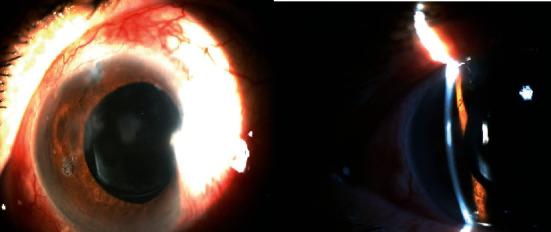

To introduce a new method for treating irido-corneal adhesion (ICA) by using argon laser. . A 60-year-old woman with advanced glaucoma who is undergoing trabeculectomy. In follow-up visits, choroidal effusion and iridocorneal adhesion were seen in the examination. The massive choroidal effusion was treated with medical therapy. In further follow-up examination, ICA was repaired with argon laser.

Early argon laser synechiolysis is a less-invasive procedure which prevents probable surgical complications such as local detachment of Descemet's membrane or bleeding in surgical synechiolysis.

介绍一种使用氩激光治疗虹膜角膜粘连(ICA)的新方法。一名60岁患有晚期青光眼且正在接受小梁切除术的女性。在随访中,检查发现脉络膜积液和虹膜角膜粘连。大量脉络膜积液采用药物治疗。在进一步的随访检查中,用氩激光修复ICA。

早期氩激光粘连松解术是一种侵入性较小的手术,可预防手术粘连松解术中可能出现的手术并发症,如Descemet膜局部脱离或出血。